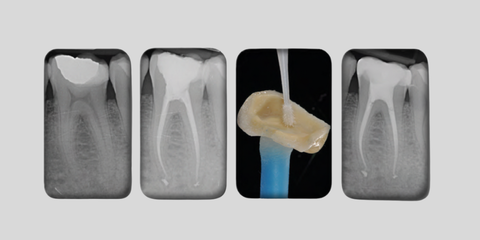

Approccio mini invasivo al trattamento endorestaurativo: nuovi paradigmi e nuovi strumenti

In collaborazione con Dentsply Sirona.